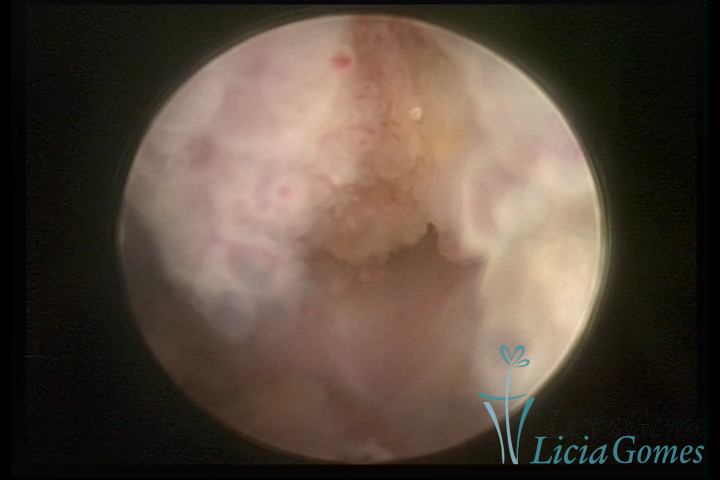

Este pode apresentar uma gama variável de aspectos macroscópicos, com aspecto pseudopolipoide; lembrando tecido cerebroide ou com reação deciduoide;a vascularização superficial é mais evidente e com vasos em formatos de saca-rolha ou espirais visualizando também a vascularização com atípias, com aumento do calibre dos vasos superficiais, pode ser encontrado também tecido em necrose, poderá haver um pequenos dendritos (papilomatoso).